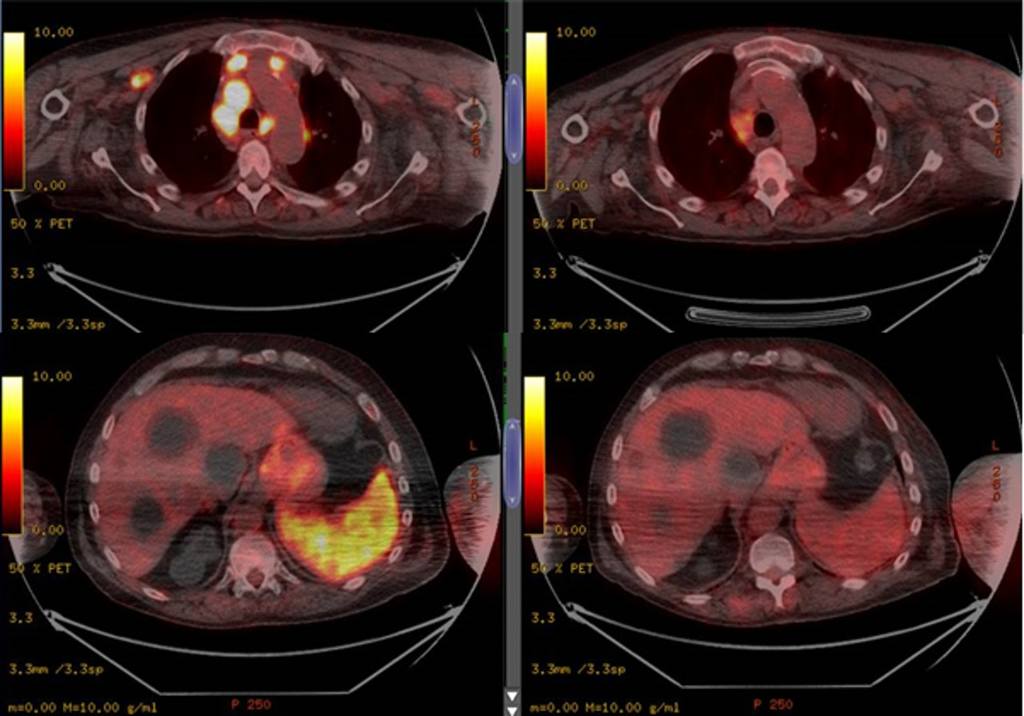

《英國血液學雜誌》(British Journal of Haematology)近日發表臨床病例報告,1名患腎衰竭

的61歲英國男子移植腎臟失敗後,3年來沒再接受免疫抑制治療。早前男子因體重銳減及淋巴結腫大

被送往醫院血液科檢查,確診霍奇金氏淋巴瘤(Hodgkin's lymphoma),癌細胞更已擴散至全身。

英國男子之後再因呼吸困難及氣促入院,不幸再被驗出對新冠病毒呈陽性反應,經過11日治療後出院。

在家休養期間,英國男子沒有獲處方免疫療法或皮質類固醇藥物。4個月後,醫護人員為男子進行

斷層掃描,竟發現他淋巴結腫大的情況有所減輕,體內腫瘤亦大規模消失,PCR腫瘤指數也大幅下降。